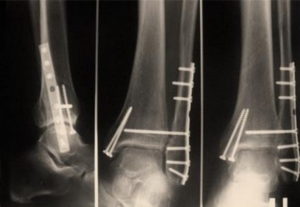

Консолидированный перелом на рентгене

- При наличии смещения костных отломков производится ручная репозиция или оперативное вмешательство с фиксацией отломков пластинами или винтами.